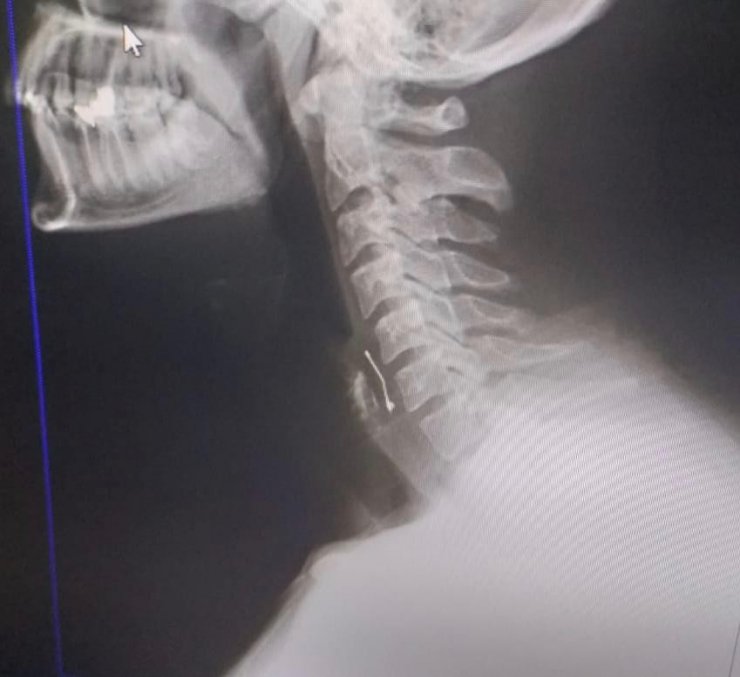

pastayı yedikten sonra fenalaşınca Kahramanmaraş Sütçü İmam Üniversitesi (KSÜ) Tıp Fakültesine götürüldü. Yapılan kontrollerde boğazına toplu iğne saplandığı tespit edilen genç, acil ameliyata alındı. Ameliyatla boğazına saplanan iğne çıkarılan Ramazan Orçan'ın tedavisi sürüyor.

Ramazan Orçan, "Perşembe akşamı arkadaşlarımla birlikte Tekerek'te bulunan bir pastaneye doğum günü kutlamak için gittik. Biraz oturduktan sonra yaş pasta masamıza geldi. Ben pastadan birkaç defa aldım. Boğazıma bir şeyin battığını ve nefes alamadığımı hissettim. Acil olarak pastaneden ayrıldık ve Kahramanmaraş Sütçü İmam Üniversite Acil Servisine geldik. Burada yapılan tetkikler sonucu boğazımda bir toplu iğne olduğu kanısına varıldı. Defalarca operasyon geçirdim. Yoğun uğraşlar sonucunda toplu iğne boğazımdan çıkarıldı. Şuan hastanede yatıyorum. Bir süre daha gözetim altında tutulacağım. Ölümle kalım arasında kaldığımı doktorlar ifade etti. Benim başıma geldi, başkalarının başına gelmesin. Olayı yargıya taşıyacağım" dedi.